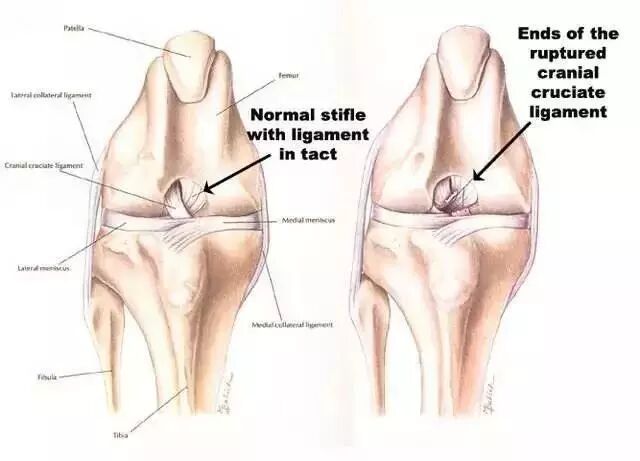

14、前十字韧带撕裂

①急性伤害(伸直过度、外翻剪力等);

②急速的渗出液(在伤害以后少于2小时)暗示着关节血肿是由于被撕裂的韧带末端流血的结果;

③无法继续运动;

④主观的不稳;

⑤阳性的Lachman测试,枢轴移动测试;

⑥阳性的前抽屉试验(较Lachman测试不敏感和特定)。